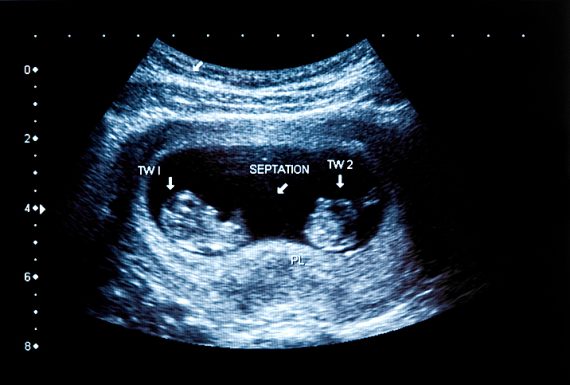

Vanishing twin syndrome: เมื่ออยู่ ๆ “แฝดในท้องหายไป”

byVanishing twin syndrome: เมื่ออยู่ ๆ “แฝดในท้องหายไป” หลาย ๆ คนน่าจะเคยได้ยินจากข่าวหรือจากที่คนพูดกันรอบตัวใช่ไหมคะ ว่าตอนแรกตรวจพบเป็นครรภ์แฝด แต่แล้วจู่ ๆ “แฝดในท้องหายไป” จากที่คาดหวังไว้ว่าจะมีลูกน้อยหน้าตาเหมือนกันถึงสองคน กลับเหลือแค่คนเดียวซะอย่างนั้น บางครั้งมารู้เอาอีกทีตอนคลอดแล้วก็มี ที่ผ่านมาเข้าใจว่าจะได้ลูกแฝดมาตลอด พอคลอดออกมา ทำไมกลับคลอดมาแค่คนเดียวได้ ปรากฏการณ์นี้เริ่มเป็นที่รู้จักในปี พ.ศ. 2488 เกิดขึ้นเมื่อฝาแฝดหายไปจากในครรภ์ วันนี้…